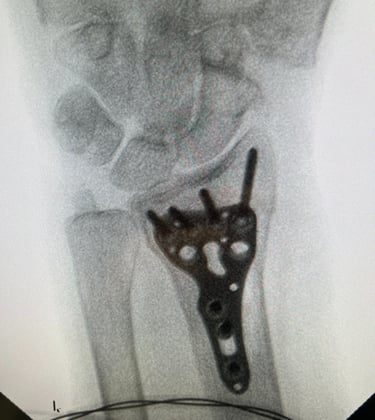

Polso e Mano

Mi occupo del trattamento delle principali patologie della mano e del polso, sia degenerative che traumatiche. Tratto condizioni frequenti come sindrome del tunnel carpale, dito a scatto, tendiniti e traumatologia della mano e del polso, con approccio conservativo o chirurgico mirato al recupero della funzionalità e alla riduzione del dolore.